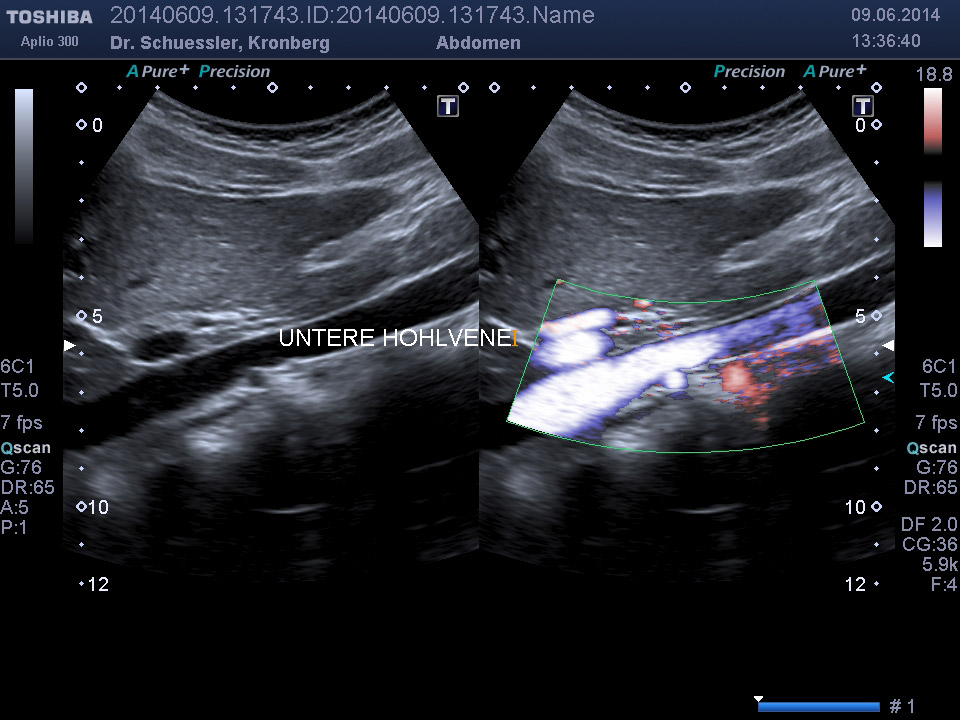

Die farbkodierte Duplexuntersuchung der Gefäße ist ein Ultraschallverfahren und gibt u.a. Auskunft über Verkalkungen, Einengungen, Verschlüsse oder Thrombosen im Bereich der Arterien und Venen.

Sie kann in allen Gefäßregionen des Körpers zur Anwendung kommen.

Die Untersuchung wird angewandt zur Diagnostik von Verengungen in den hirnversorgenden Arterien, Erweiterungen (Aneurysmen) oder Verengungen der Bauchschlagader, Verengungen der Nierenarterien bei Bluthochdruck,  Venenthrombosen und zur Bestimmung des Gefäßrisikoprofils.